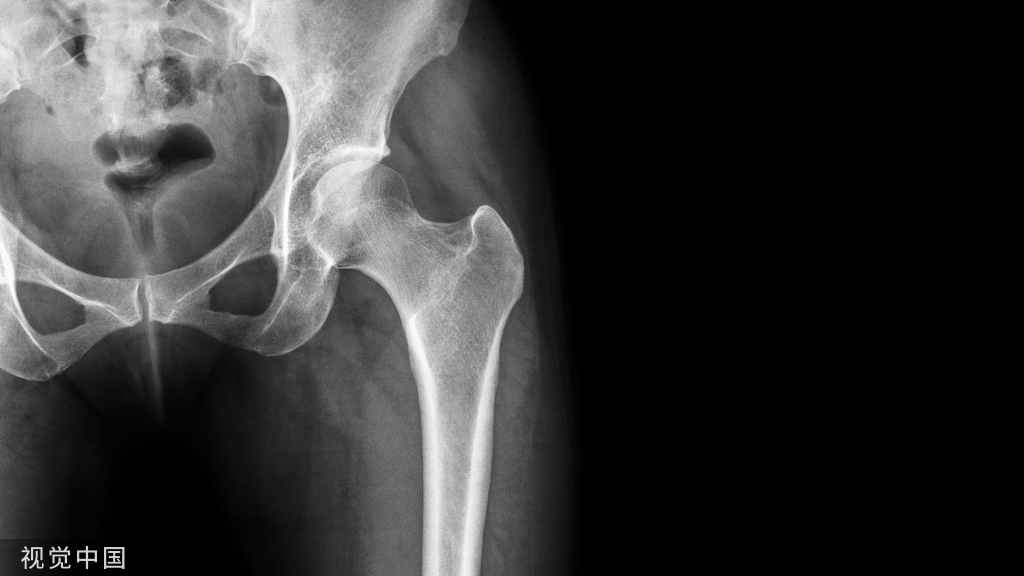

2022十大热门骨科创新技术

本文汇总的十大产品排名依据为文章的阅读量,按阅读量排名如下: